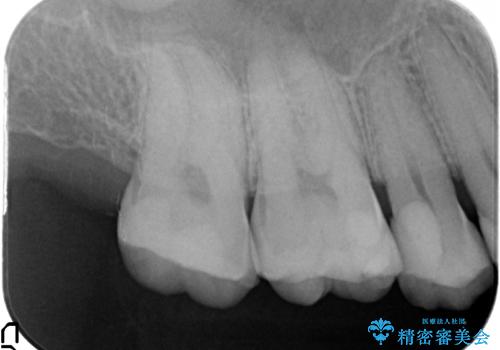

- 以前に治療を行った銀歯がしみることの改善を希望して来院されました。

銀歯辺縁からのセメント漏洩が認められたため、セラミックインレーによる精度の高い修復を行うこととなりました。

辺縁の漏洩について

修復物の精度が悪いと、接着材であるセメントが漏出し痛みが生じることがあります。

劣化の速度が遅い材料を用いて、精度の高い修復を行うことで長期的な予後が期待できます。